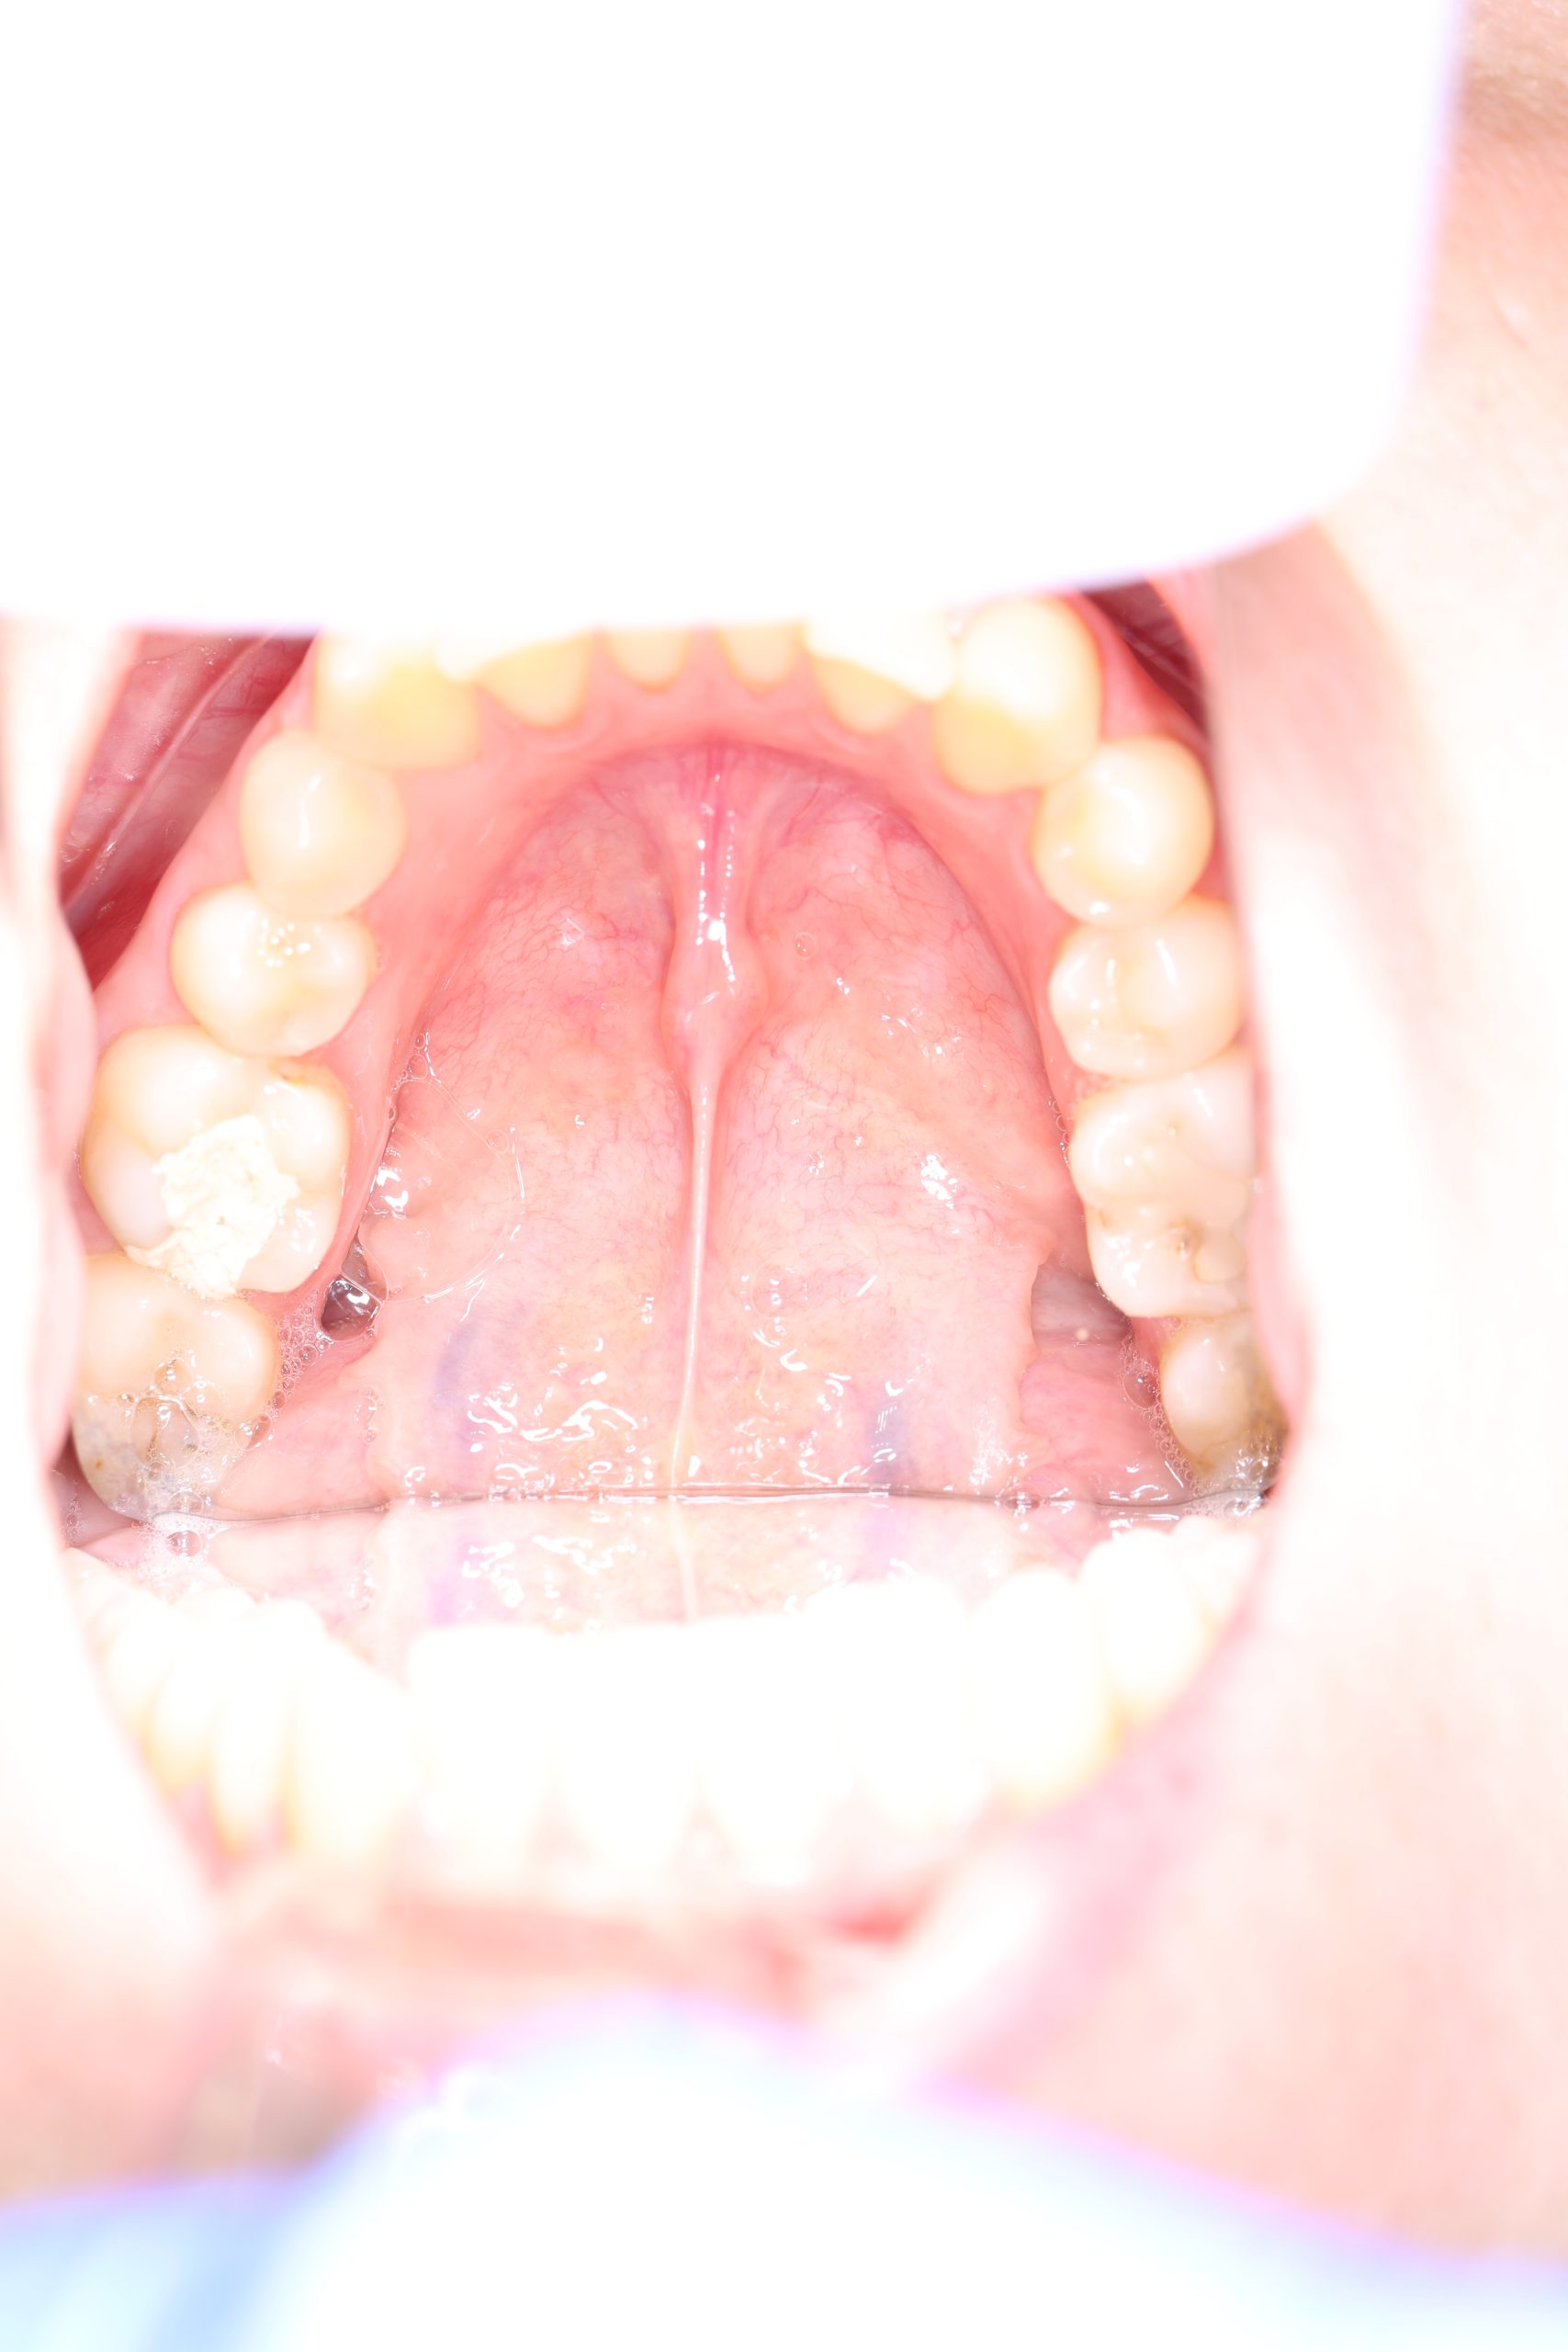

Once numb, most patients feel only light vibration and pressure. Even severe toothache typically eases immediately after anaesthesia takes effect. - Microscope-guided access

Under bright magnified light, a tiny opening is created and every canal located — even the hidden ones that often cause failures elsewhere. - Cleaning and shaping